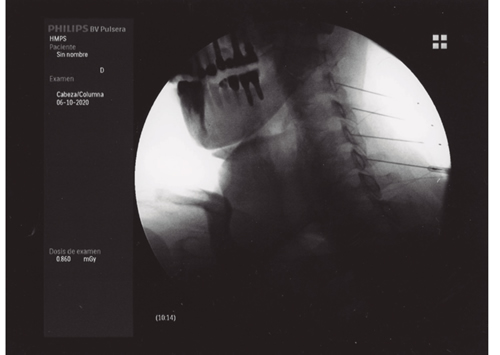

Figura 1